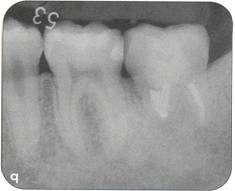

Fi 545e45f gs 5-2p and 5-2q Two years 5 months after transplantation. The donor tooth is restored with composite resin. |

Restorative treatment Unnecessary tooth reduction can be avoided by careful restorative treatment planning (see Fi 545e45f gs 5-1, 5-4, and 5-6). Surgical procedure |